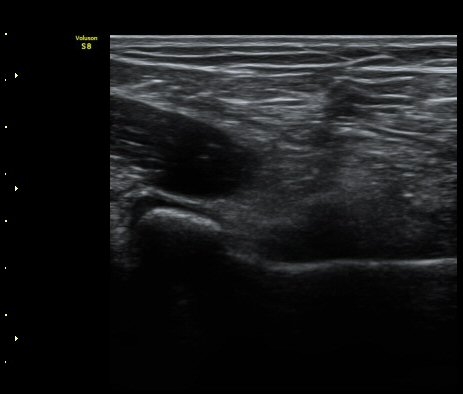

ÆÈ²ÞÄ¡ ³»Ãø¿¡¼­ ½ÃÇàÇÑ ¿ä°ñµÎ Á¾´Ü¸é°Ë»ç¿¡¼­ ¿ä°ñµÎ ÇÇÁú°ñÀÇ ºÒ±ÔÄ¥º¯È­(irregularity)°¡

°üÂûµÇ¾î ¼Õ»óÀÌ ÃßÁ¤µÊ(±×¸² 3)

¾Æ·§ÆÈÀ» µ¹¸®¸é¼­ ¿ä°ñµÎ Ⱦ´Ü¸é°Ë»ç ½Ã ¿ä°ñµÎ ÇÇÁú°ñ ¿¬°á¼º ¼Ò½ÇÀÌ °üÂûµÊ(±×¸² 5)

¾Æ·§ÆÈ µ¹¸®¸é¼­ ¿ä°ñµÎÀÇ ¿òÁ÷ÀÓ°ú °ñÀý¼± ³ëÃâÀÌ µ¿¿µ»ó¿¡¼­ ¶Ñ·ÈÇÔ(÷ºÎ ÆÄÀÏ).